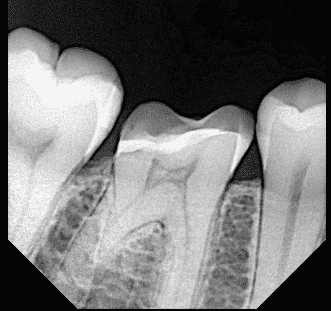

Pre-operative x ray

After D.M.E

Post operative x ray , you can see the fitness